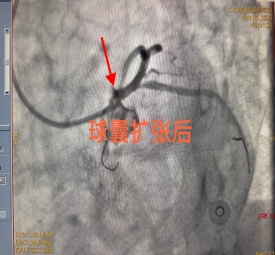

时间就是生命,时间就是希望。面对这一危急病例,科室立即启动急诊绿色通道,以最快速度全力推进诊治。急诊冠脉造影检查结果令人心惊:患者冠状动脉左主干狭窄程度高达95%。左主干是心脏冠状动脉的核心血管,被称为“生命主干道”,起源于主动脉根部,分支为前降支和回旋支,负责为左心室(心脏主要泵血结构)提供 75% 的血液供应。左主干病变是指冠状动脉左主干(LM)发生≥50%的狭窄,属于高危冠心病范畴。该病症病情凶险,若处理不当,极易引发猝死、大面积心肌梗死、心源性休克等严重后果。

该患者左主干狭窄95%,病情凶险程度极高,堪称“生死一线间”,需立即手术。在征求患者及家属意见后,各部门高效协同联动,着手准备手术。

手术台上,每一个操作都精准无误,每一步决策都果断坚定。在生死竞速的关键时刻,心血管内科三病区杨金勇副主任团队默契配合、沉着应战,凭借精湛的技术成功为患者实施介入治疗,开通了重度狭窄的血管,恢复了心脏正常供血。整个手术过程十分顺利,患者胸痛症状迅速缓解,生命体征趋于平稳,成功脱离生命危险,目前已顺利出院。